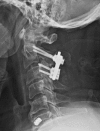

Fractures of the second cervical vertebra (C2, axis) are common in adult spine surgery. Those fractures occurring in younger adult patients are often associated with high-energy mechanism trauma, resulting in a "Hangman's Fracture." Management of these fractures is often successful with nonoperative means, though surgery may be needed in those fractures with greater displacement and injury to the C2-C3 disc. Older patients are more likely to sustain fractures of the odontoid process. The evidence supporting surgical management of these fractures is evolving, as there may be a mortality benefit to surgery. Regardless of treatment, longer-term mortality rates are high in this patient population, which should be discussed with the patient and family at the time of injury. Pediatric patients may suffer fractures of the axis, though differentiation of normal and pathologic findings is necessary and more difficult with the skeletally immature spine.